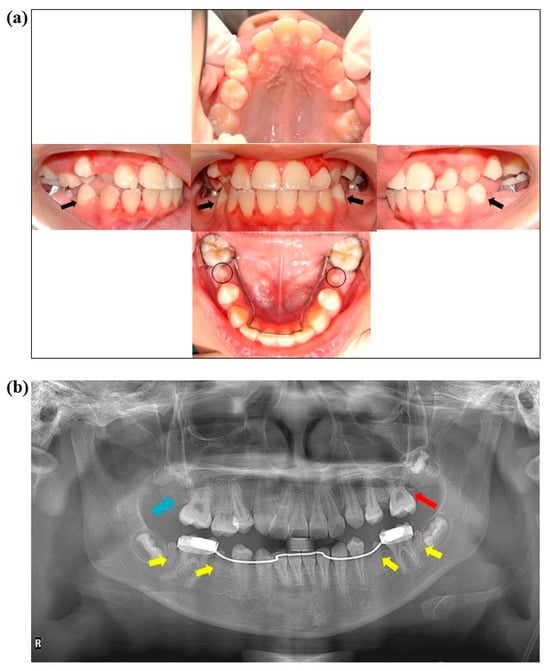

In May 2022, at the age of 12 years, the patient returned to the clinic for a dental evaluation before orthodontic treatment. Examination of intraoral (Figure 2a) and radiograph pictures (Figure 2b) revealed microdontia in tooth numbers 35, 37, 45, and 47 (Figure 2b, yellow arrows). It was also observed that tooth numbers 17 and 27 were missing (Figure 2b, blue and red arrows, respectively). Cervical lines on enamel (chronological hypoplasia) were found in all first permanent premolars (Figure 2a, black arrows). The overall oral hygiene could be rated as “fair” due to generalized gingivitis associated with the presence of biofilm with no carious lesions (Figure 2a). The orthodontist recommended removing the microdontic teeth, since they were non-functional, to facilitate the alignment of the other teeth.

Figure 2. These images were taken of the patient at age 12, five years after completing dental treatment. (a) Intraoral pictures show microdontia on tooth numbers 35 and 45 (black circles). Black arrows show the cervical line on the enamel of tooth numbers 34 and 44 (chronological hypoplasia). A lingual holding arch was placed on the lower arch to prevent mesial shift of tooth numbers 36 and 46. (b) This panoramic radiograph was taken after the completion of dental treatment. It shows a DMFT of 0 on permanent teeth. The yellow arrows show microdontia on tooth numbers 35, 37, 45, and 47. The blue arrow shows where tooth number 17 is missing, and the red arrow shows a minor calcification mass on tooth number 27.